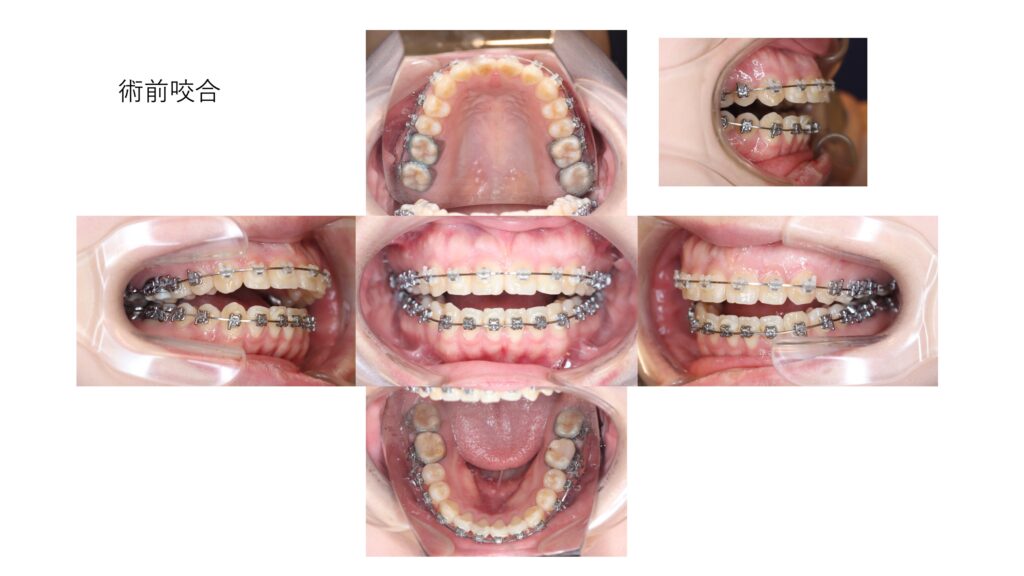

この方は、前歯がかみ合わずにすき間があいてしまう「開咬(かいこう)」の状態でした。

術後は前歯のすき間がなくなり、しっかりとかみ合う状態になりました。